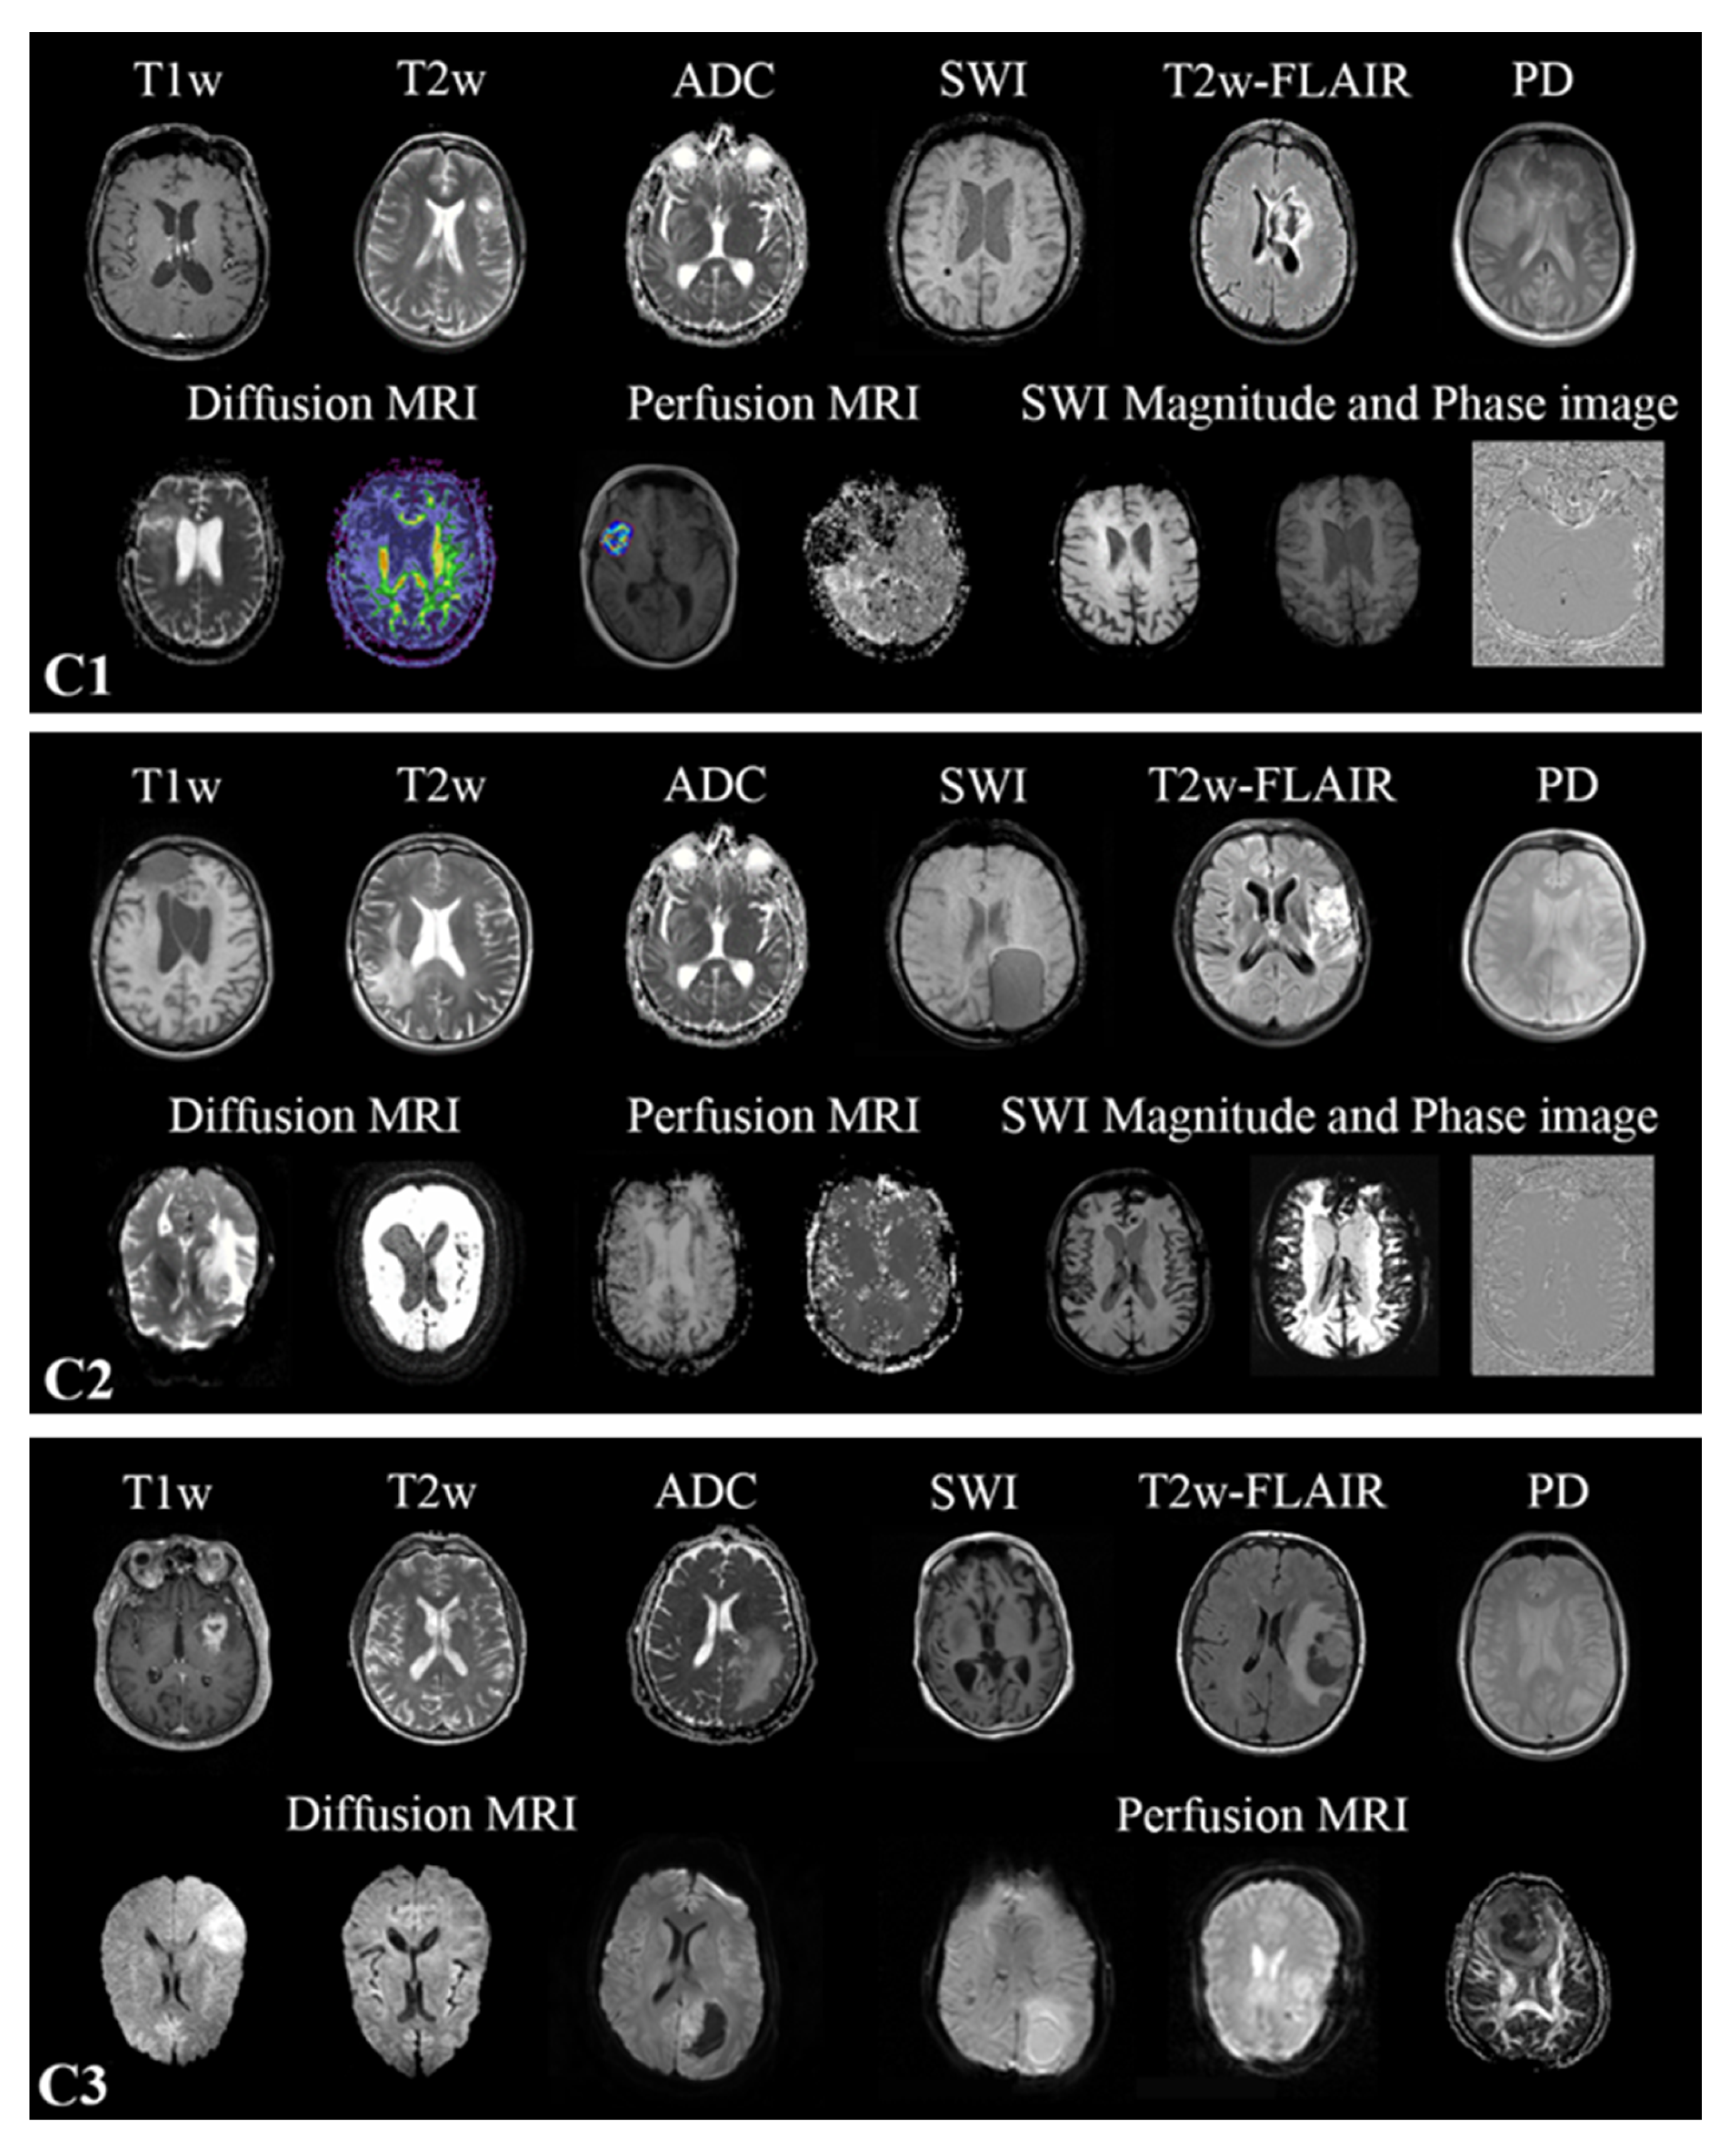

2.2. MR Scans